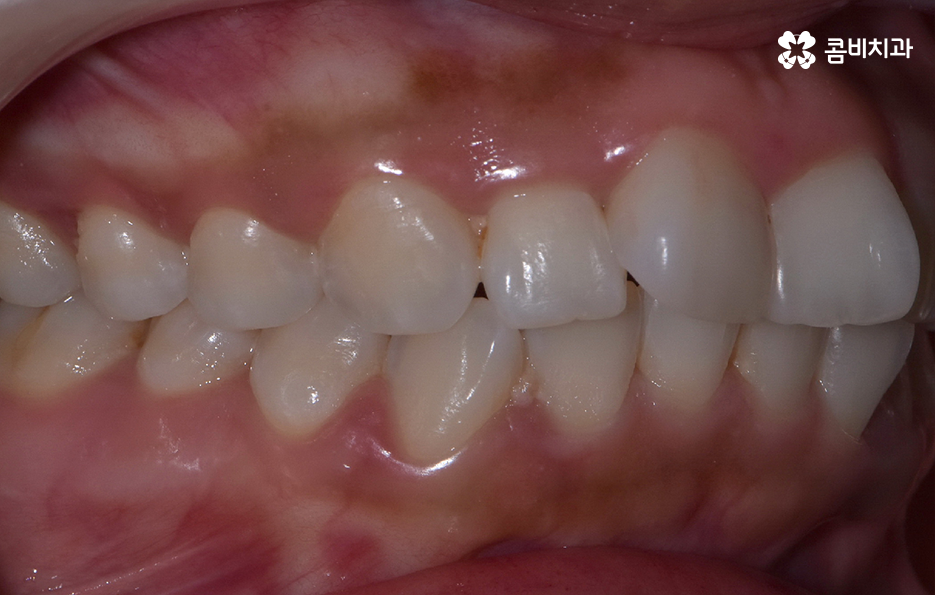

이처럼 교정을 결심하게 되는 계기는 다양한데 그 중에서도 앞니 틀어짐 교정 방법은 그 정도에 따라서 치료 방법이 다양하다 보니 어떤 분들은 비교적 간단한 치료가 가능하고 어떤 분들은 전체교정을 해야 하다보니 치료 방법의 갭차이를 크게 느끼시는 분들도 많이 있는데요

특히 앞니는 사람의 첫인상과 발음을 결정짓는 중요한 치아라 조금만 틀어져도 눈에 잘 띄고, 스스로도 불편함을 크게 느끼게 되는데 앞니 틀어짐 교정 방법의 차이는 기본적으로는 치열의 복잡성이나 치아가 이동해야 하는 정도, 교합 등의 차이에서 나타나기 때문에 치료 방법을 구체적으로 이해하기 위해서는 앞니가 틀어지는 원인과 치아교정의 원리를 알아가는 것이 도움이 될 거예요

앞니가 틀어지는 원인부터 살펴보면 대표적인 원인은 치열 공간의 부족으로 치아는 제자리에 가지런히 놓이기 위해 충분한 공간이 필요한데, 치아 크기는 정상인데 턱뼈가 작거나, 젖니가 너무 일찍 빠져 앞니가 원하는 방향으로 자리 잡지 못하면 틀어짐이 쉽게 나타날 수 있어요

특히 앞니는 치열에서 먼저 눈에 띄는 자리라 공간이 조금만 부족해도 서로 밀리며 비틀리거나, 한쪽으로 회전하는 형태로 틀어지는데 어린 시절 안좋은 습관이나 편작 습관이 있던 사람들도 턱뼈 성장 불균형이 나타나 치열 공간이 부족해지는 일이 나타날 수 있었어요

앞니 틀어짐 교정 방법 경미한 수준일 때는 부분 교정 방식은 치료 기간이나 방법 면에서 비교적 간단한 치료가 가능한데 앞니 6개 정도에만 브라켓을 부착해 미세한 틀어짐을 바로잡는 방식으로 치아가 크게 회전하지 않았거나 공간이 약간 부족한 정도라면 효과적이며 기간도 보통 3~6개월로 짧은 편으로 이 방식은 앞니 배열을 빠르게 정리하면서도 자연스러운 라인을 만들 수 있어요.

다만 부분교정 방식은 교합 문제까지 해결하기는 어렵기 때문에 교합이 안정적인 경우에 적합하기에 경미한 케이스에 적합하다고 한정 지을 수 있었어요

부분교정과 투명교정 방식은 대표적으로 앞니 틀어짐이 경미한 수준일 때 적용하기 적합한 방식이지만 교합의 개선과 얼굴형의 변화를 목표로 해야하는 경우라면 환자 분들이 앞니만 고치는 것을 원한다고 해도 전체교정이 필요한 케이스도 많기 때문에 우선적으로 정밀검진을 통해서 나에게 적합한 치료 계획을 세우는 것이 중요하겠고 치아교정의 목적에는 치료 후의 지속성, 안정성 또한 함께 고려해야 한다는 점에서 앞니 틀어짐의 원인을 개선하여 재발을 방지하는 것까지도 잘 고려하실 필요가 있었어요